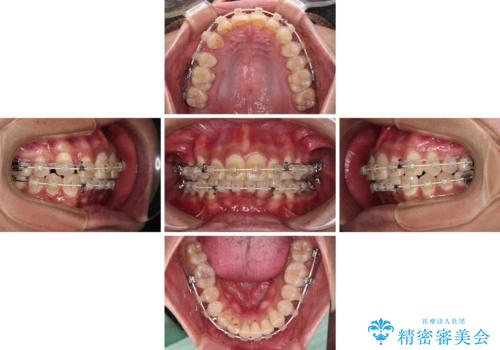

- 深い咬み合わせと前歯のデコボコを改善したいとのことで来院された患者様です。

口元の突出感はないものの、上顎前歯のデコボコが著しく、右側の咬み合わせがずれていたため、上顎右側第一小臼歯1本を抜歯することとしました。

咬合力が非常に強く、抜歯したスペースがなかなか閉じないであろうことは予想できましたが、思っていた以上に期間がかかりました。

前歯のすり減りも著しかったため、仕上げの位置の調整にも期間を要しました。